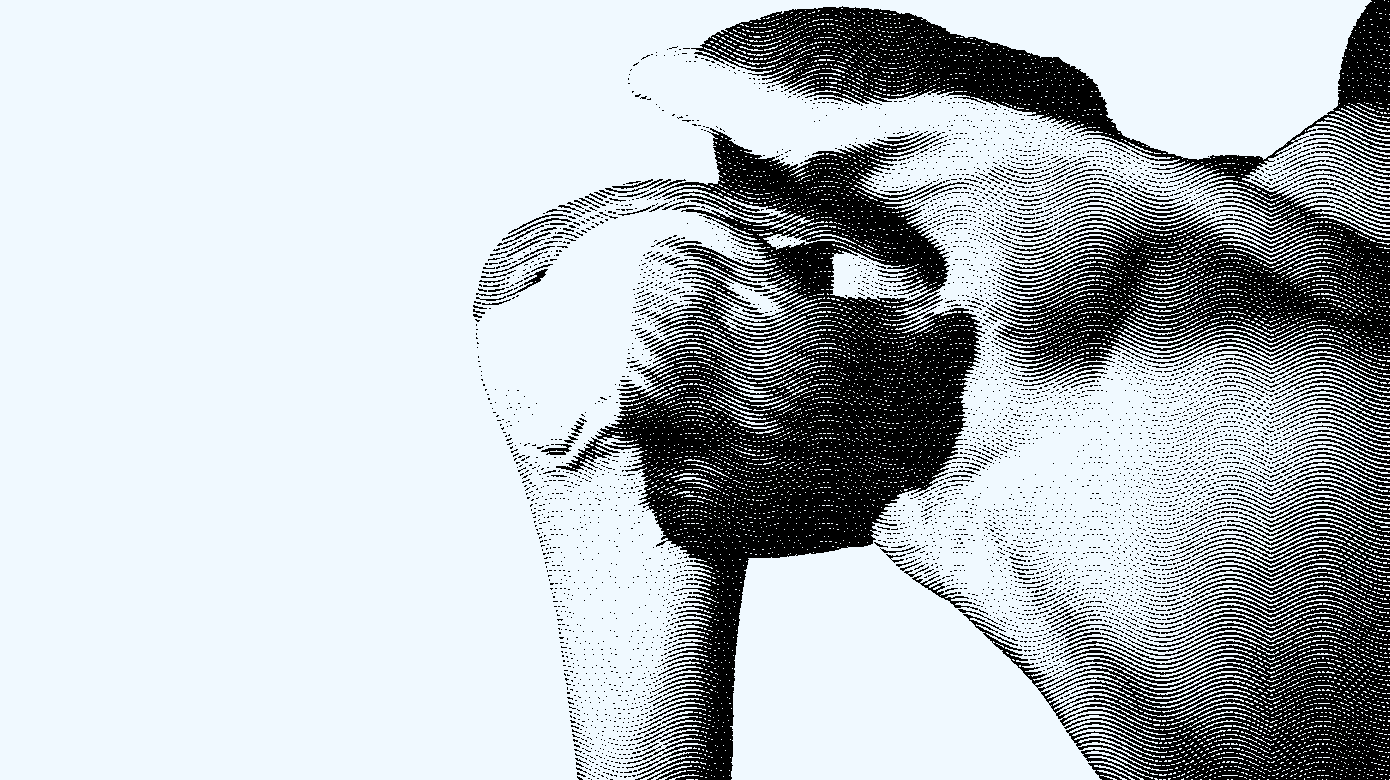

Rotator cuffen består af fire muskler: supraspinatus, infraspinatus, subscapularis og teres minor (Figur 1). De udspringer alle fra scapula og insererer sig på caput humeri i tæt relation til hinanden. Musklerne medvirker til bevægelse af skulderen i hver deres trækretning (Figur 2), men har også en vigtig dynamisk stabiliserende effekt, der sikrer centralisering af caput humeri i cavitas glenoidale [1]. En velfungerende muskulær koordination er en forudsætning for, at skulderen kan bevæges fuldt og smertefrit.